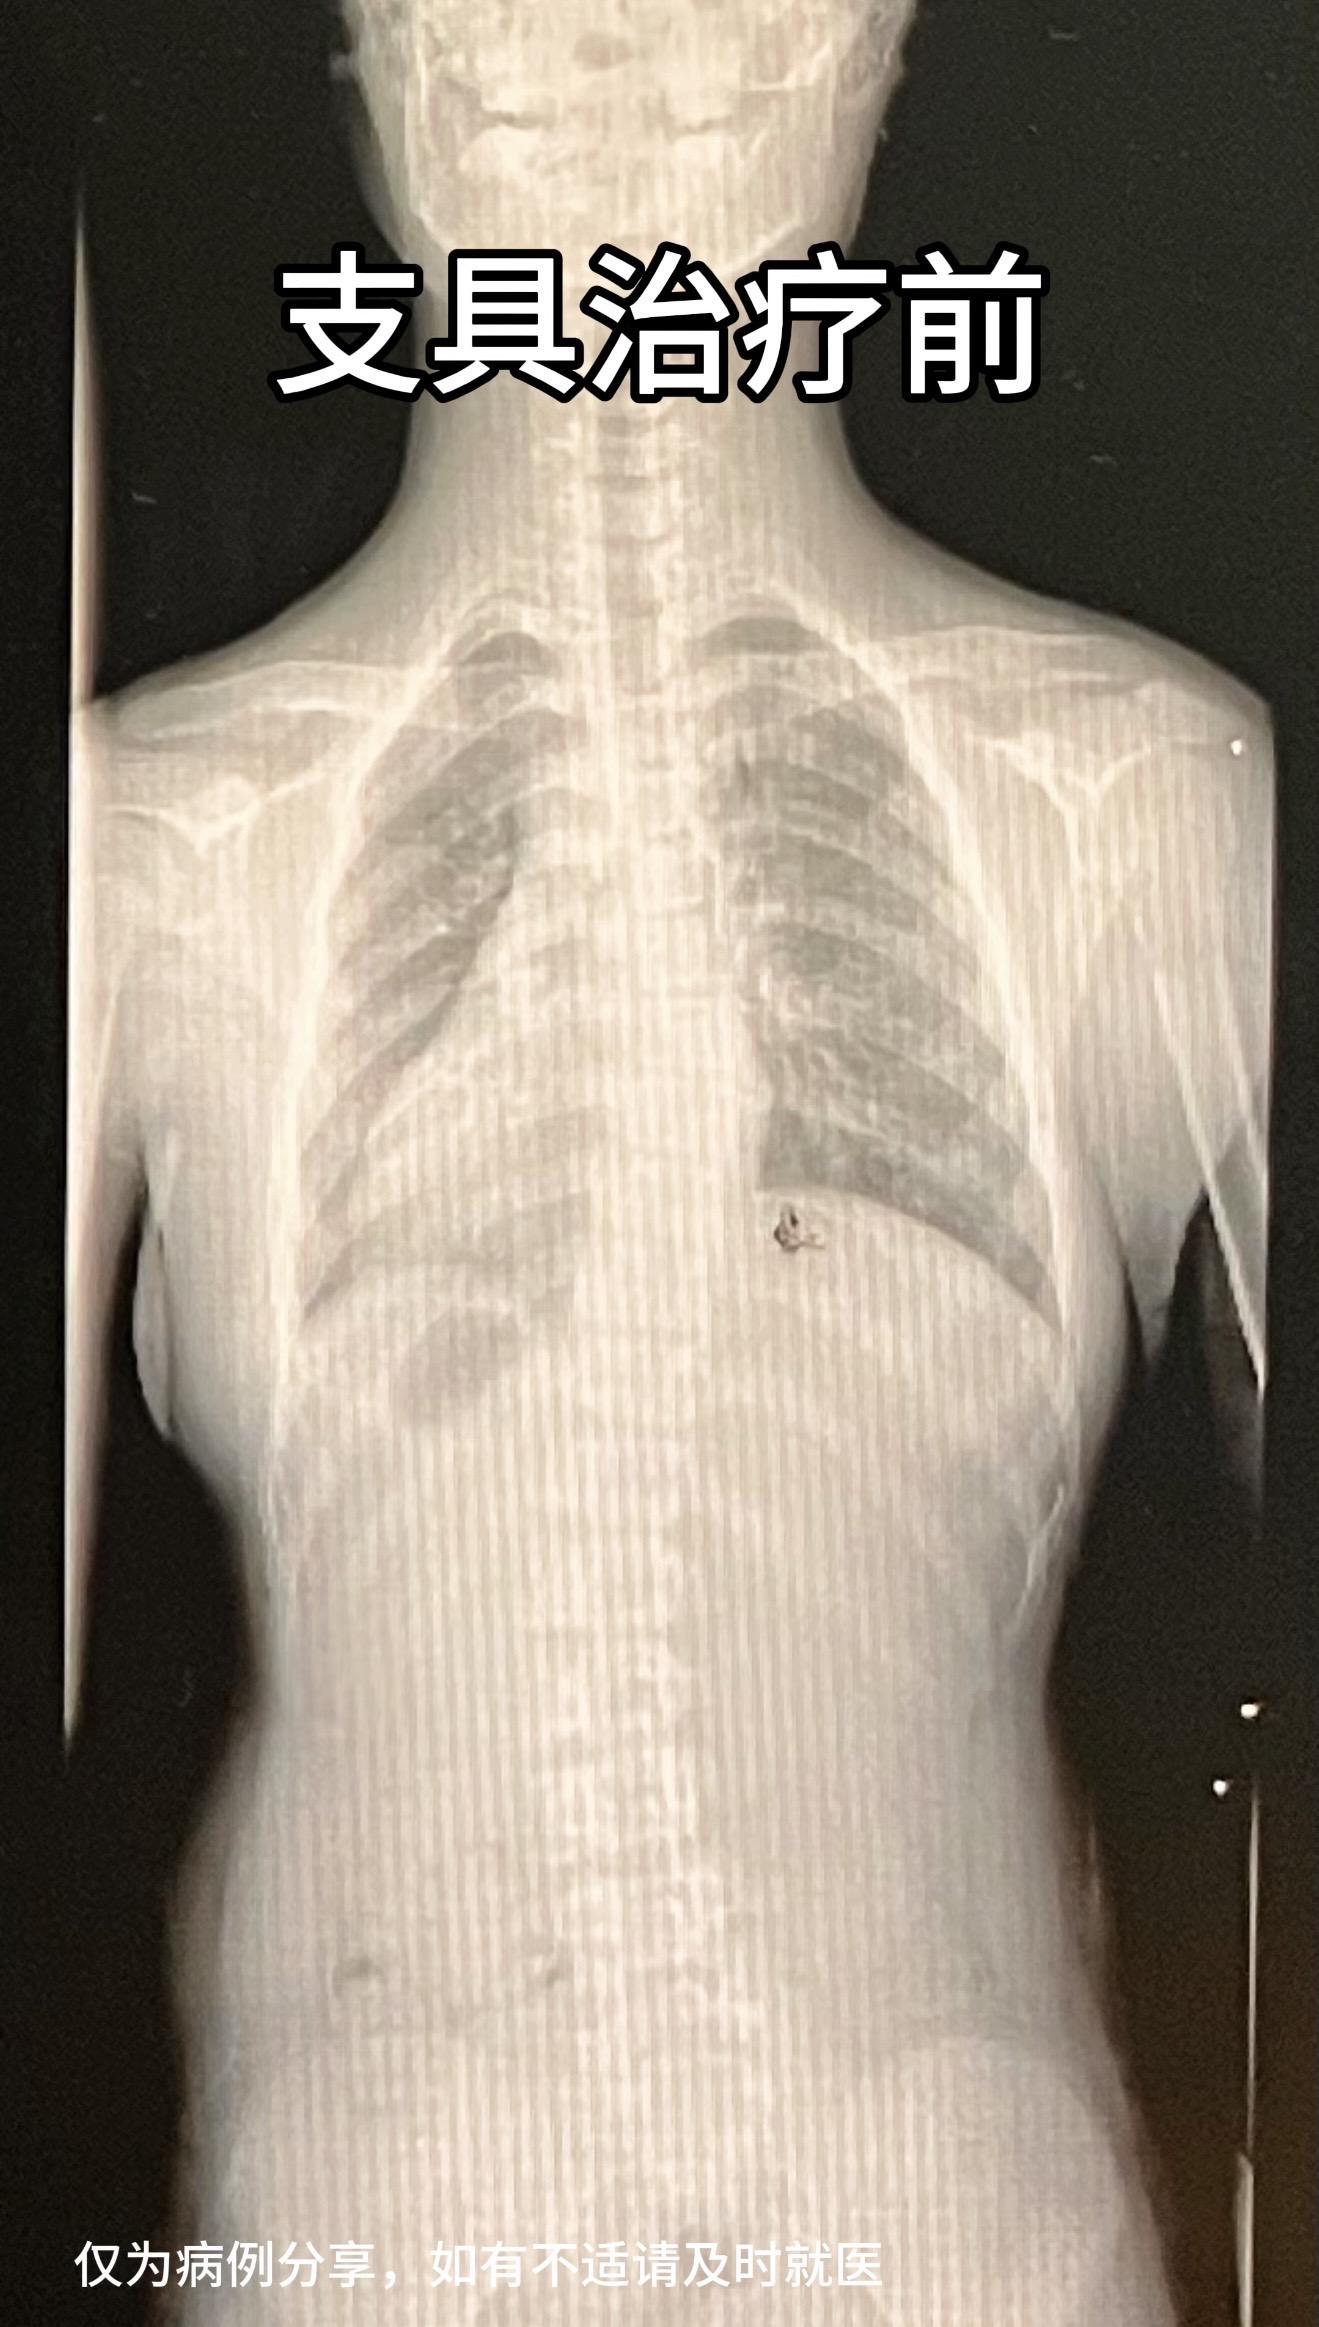

11岁女孩,近3月侧弯加重4度,支具治疗中,支具即时矫正效果好。定期复查中。